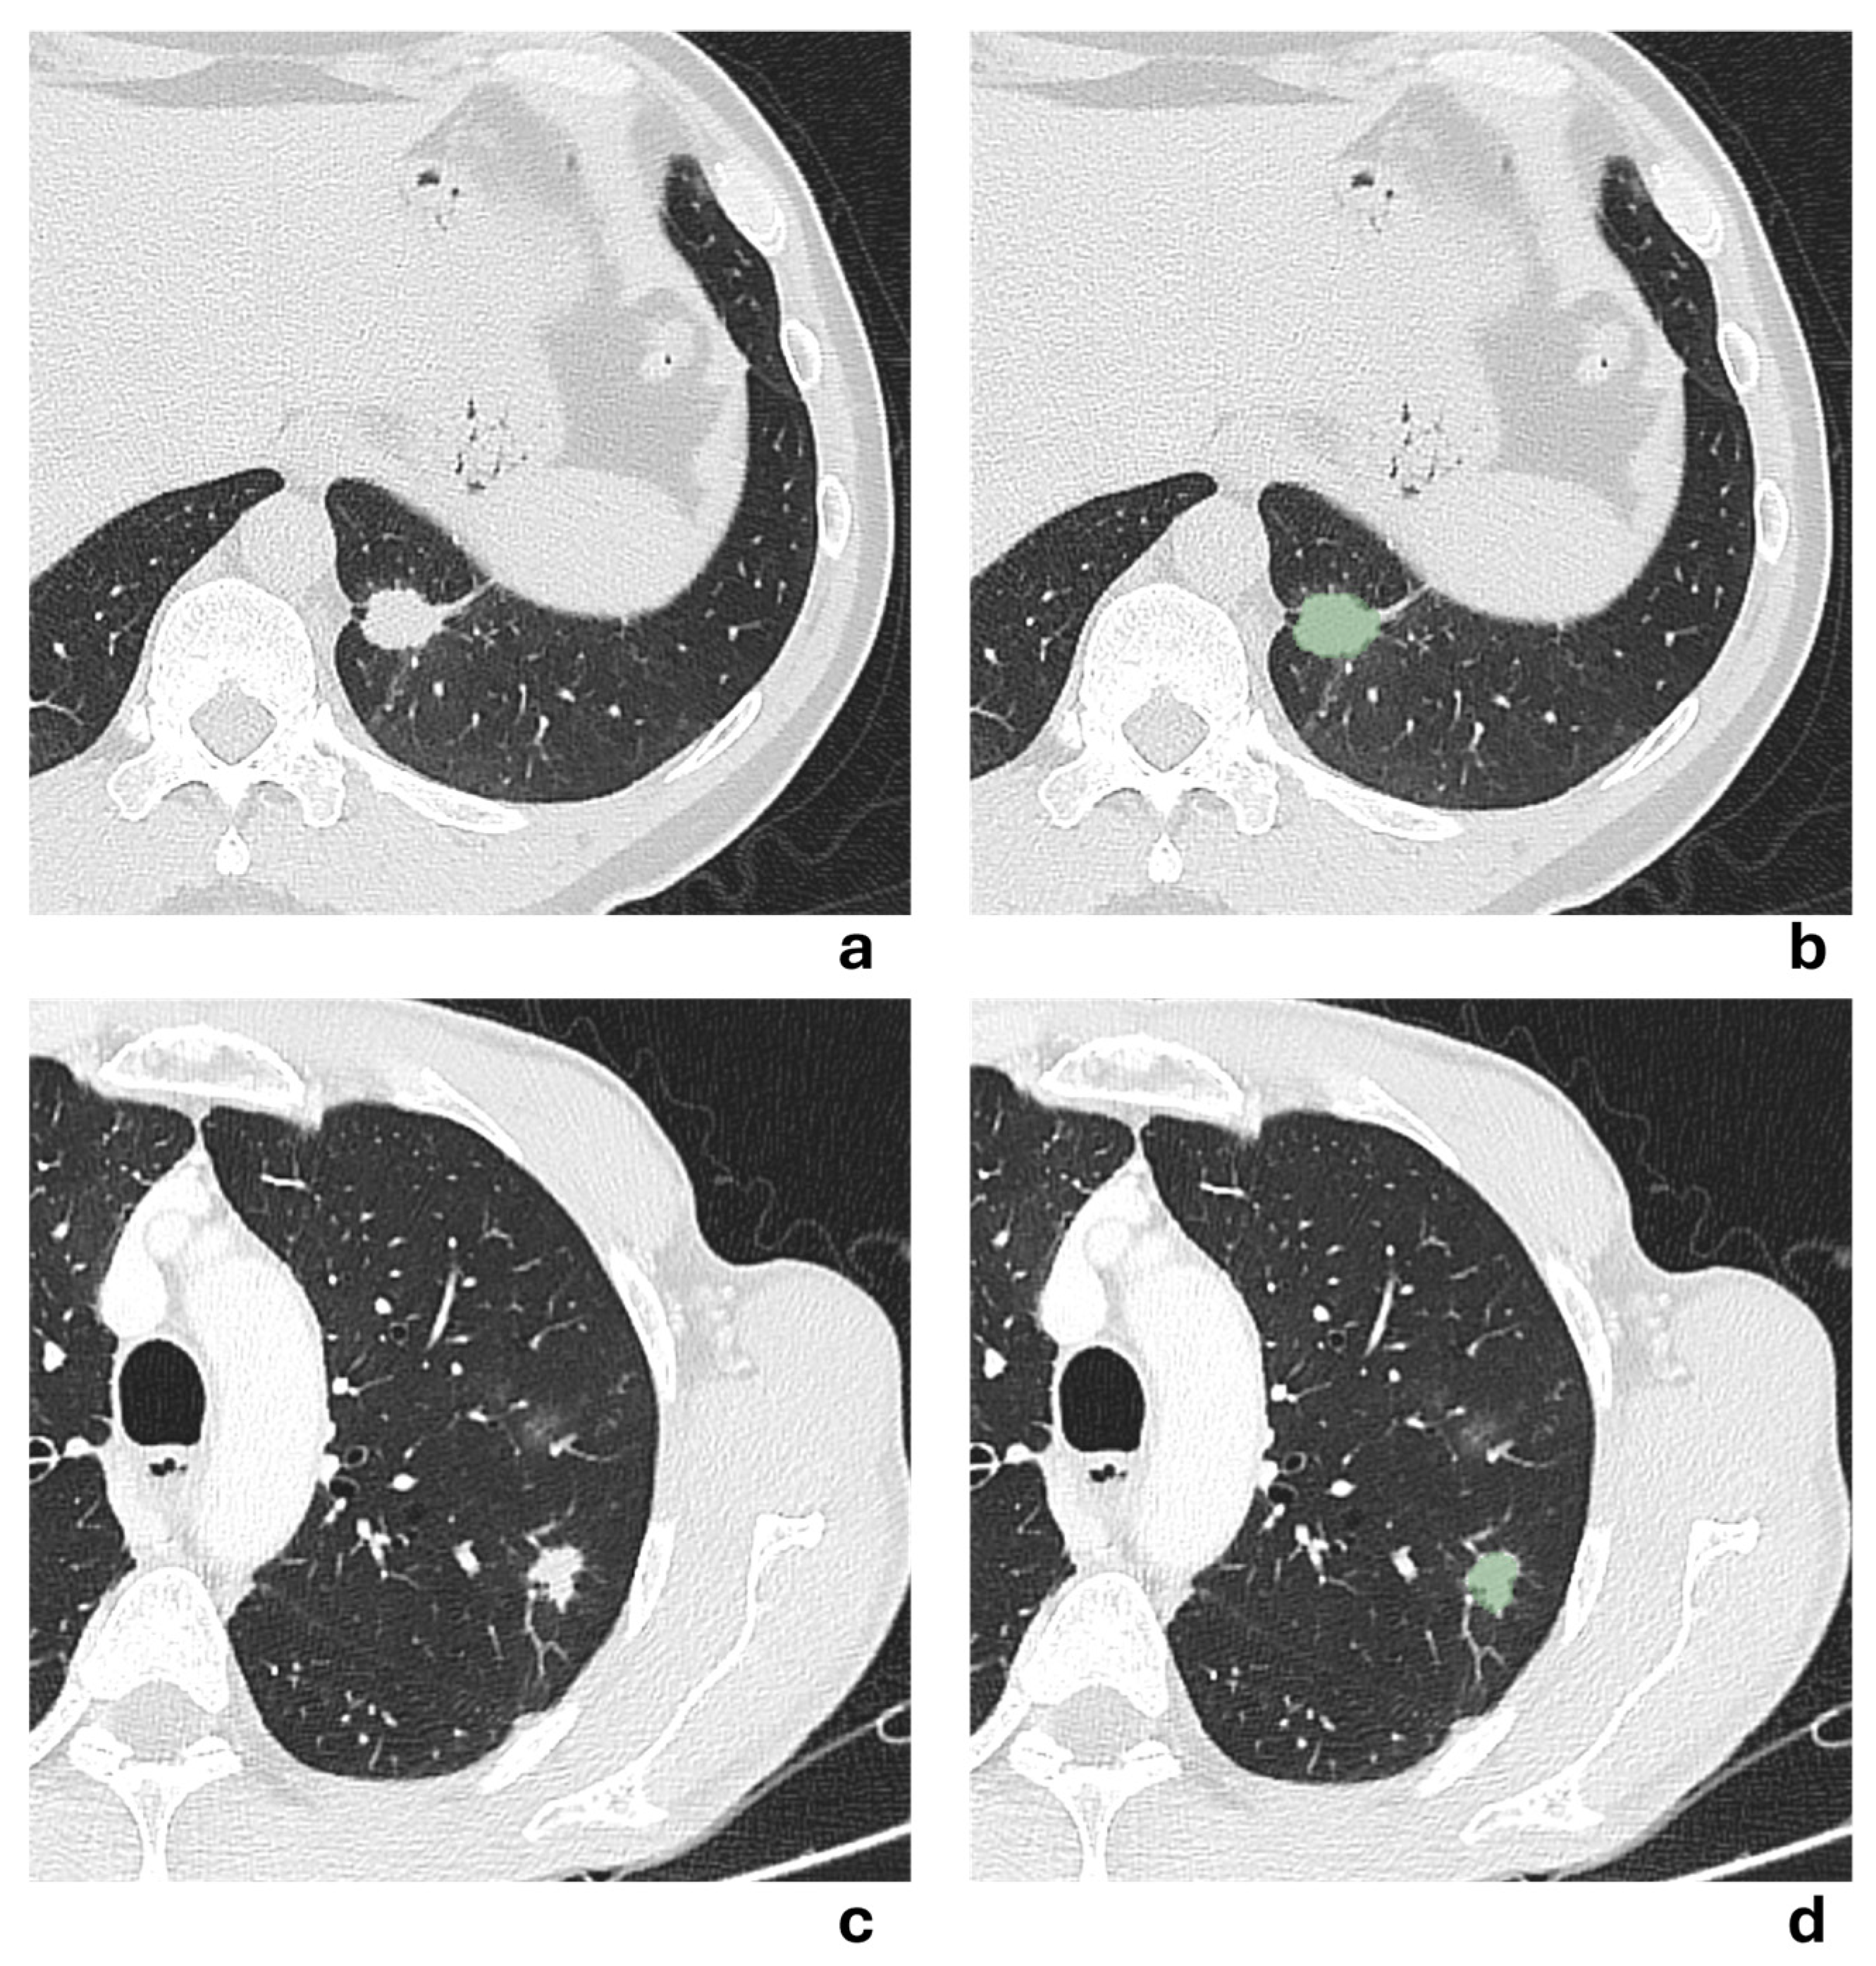

Two representative NSCLCS cases with tumor major axis < 3 cm are illustrated in Figure 5. In the first case (a-b), the presence of pleural tag suggested a radiological suspicion of pleural invasion, but it was not confirmed by histological examination. In the second case (c-d), no radiological suspicion of pleural invasion was raised due to the absence of pleural tag, but histological examination revealed pleural invasion. All models failed to correctly predict the presence of pleural invasion, except for the 3 mm-peritumoral radiomic model.

Figure 5. (a–b) Axial chest CT scan in lung window of a 54-year-old man showing a solid irregular nodule in the anteromedial basal segment of the left lower lobe, with evidence of a pleural tag sign, measuring 14.4 mm in major axis. The corresponding segmented lesion is shown in (b). Despite radiological suspicion, histological examination revealed no pleural invasion. (c-d) Axial chest CT scan in lung window of a 65-year-old man showing a solid irregular nodule in the apical segment of the left lower lobe, without evidence of pleural tag sign, measuring 22.3 mm in major axis. The corresponding segmented lesion is shown in (d). Histological examination revealed pleural invasion, despite no radiological evidence being suspected.